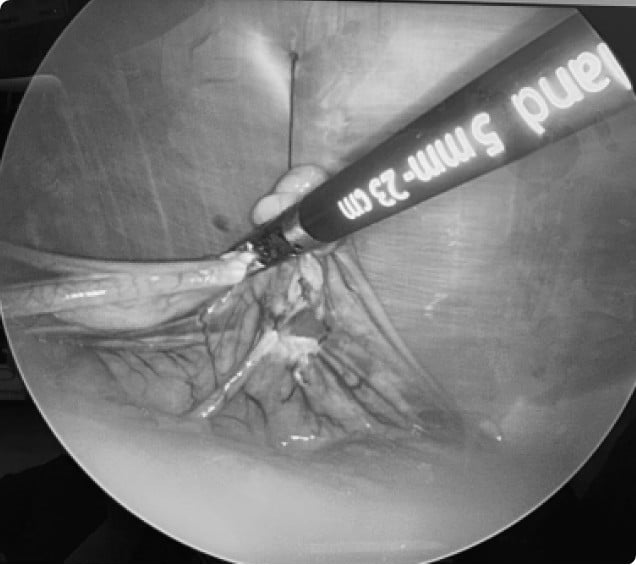

고해상도 복강경 카메라와 특수 기구를 활용해

내부 장기를 세밀하게 확인하고 안전하게 수술

강경 중성화 수술은 복부에 작은 절개창만을 통해 내시경 기구를 삽입하여 진행하는 최소침습 수술.

연부 조직 손상을 최소화해 통증과 회복 부담을 줄이고, 감염 위험까지 낮춘 안전한 수술법.